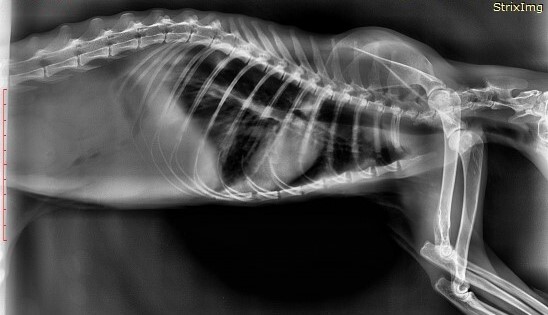

Большая часть зайчат умирает "внезапной смертью" вызванной отказом работы внутренних органов, сопровождаемым сильными болевыми ощущениями. Это происходит от обострения хронических проблем, которые копились из-за ошибок в выращивании (некрозы жкт, кровоизлияния в сердечно-сосудистой системе, переломы, защемления нервов, болезни ЦНС и другое). Дикие животные инстинктивно скрывают любое недомогание.